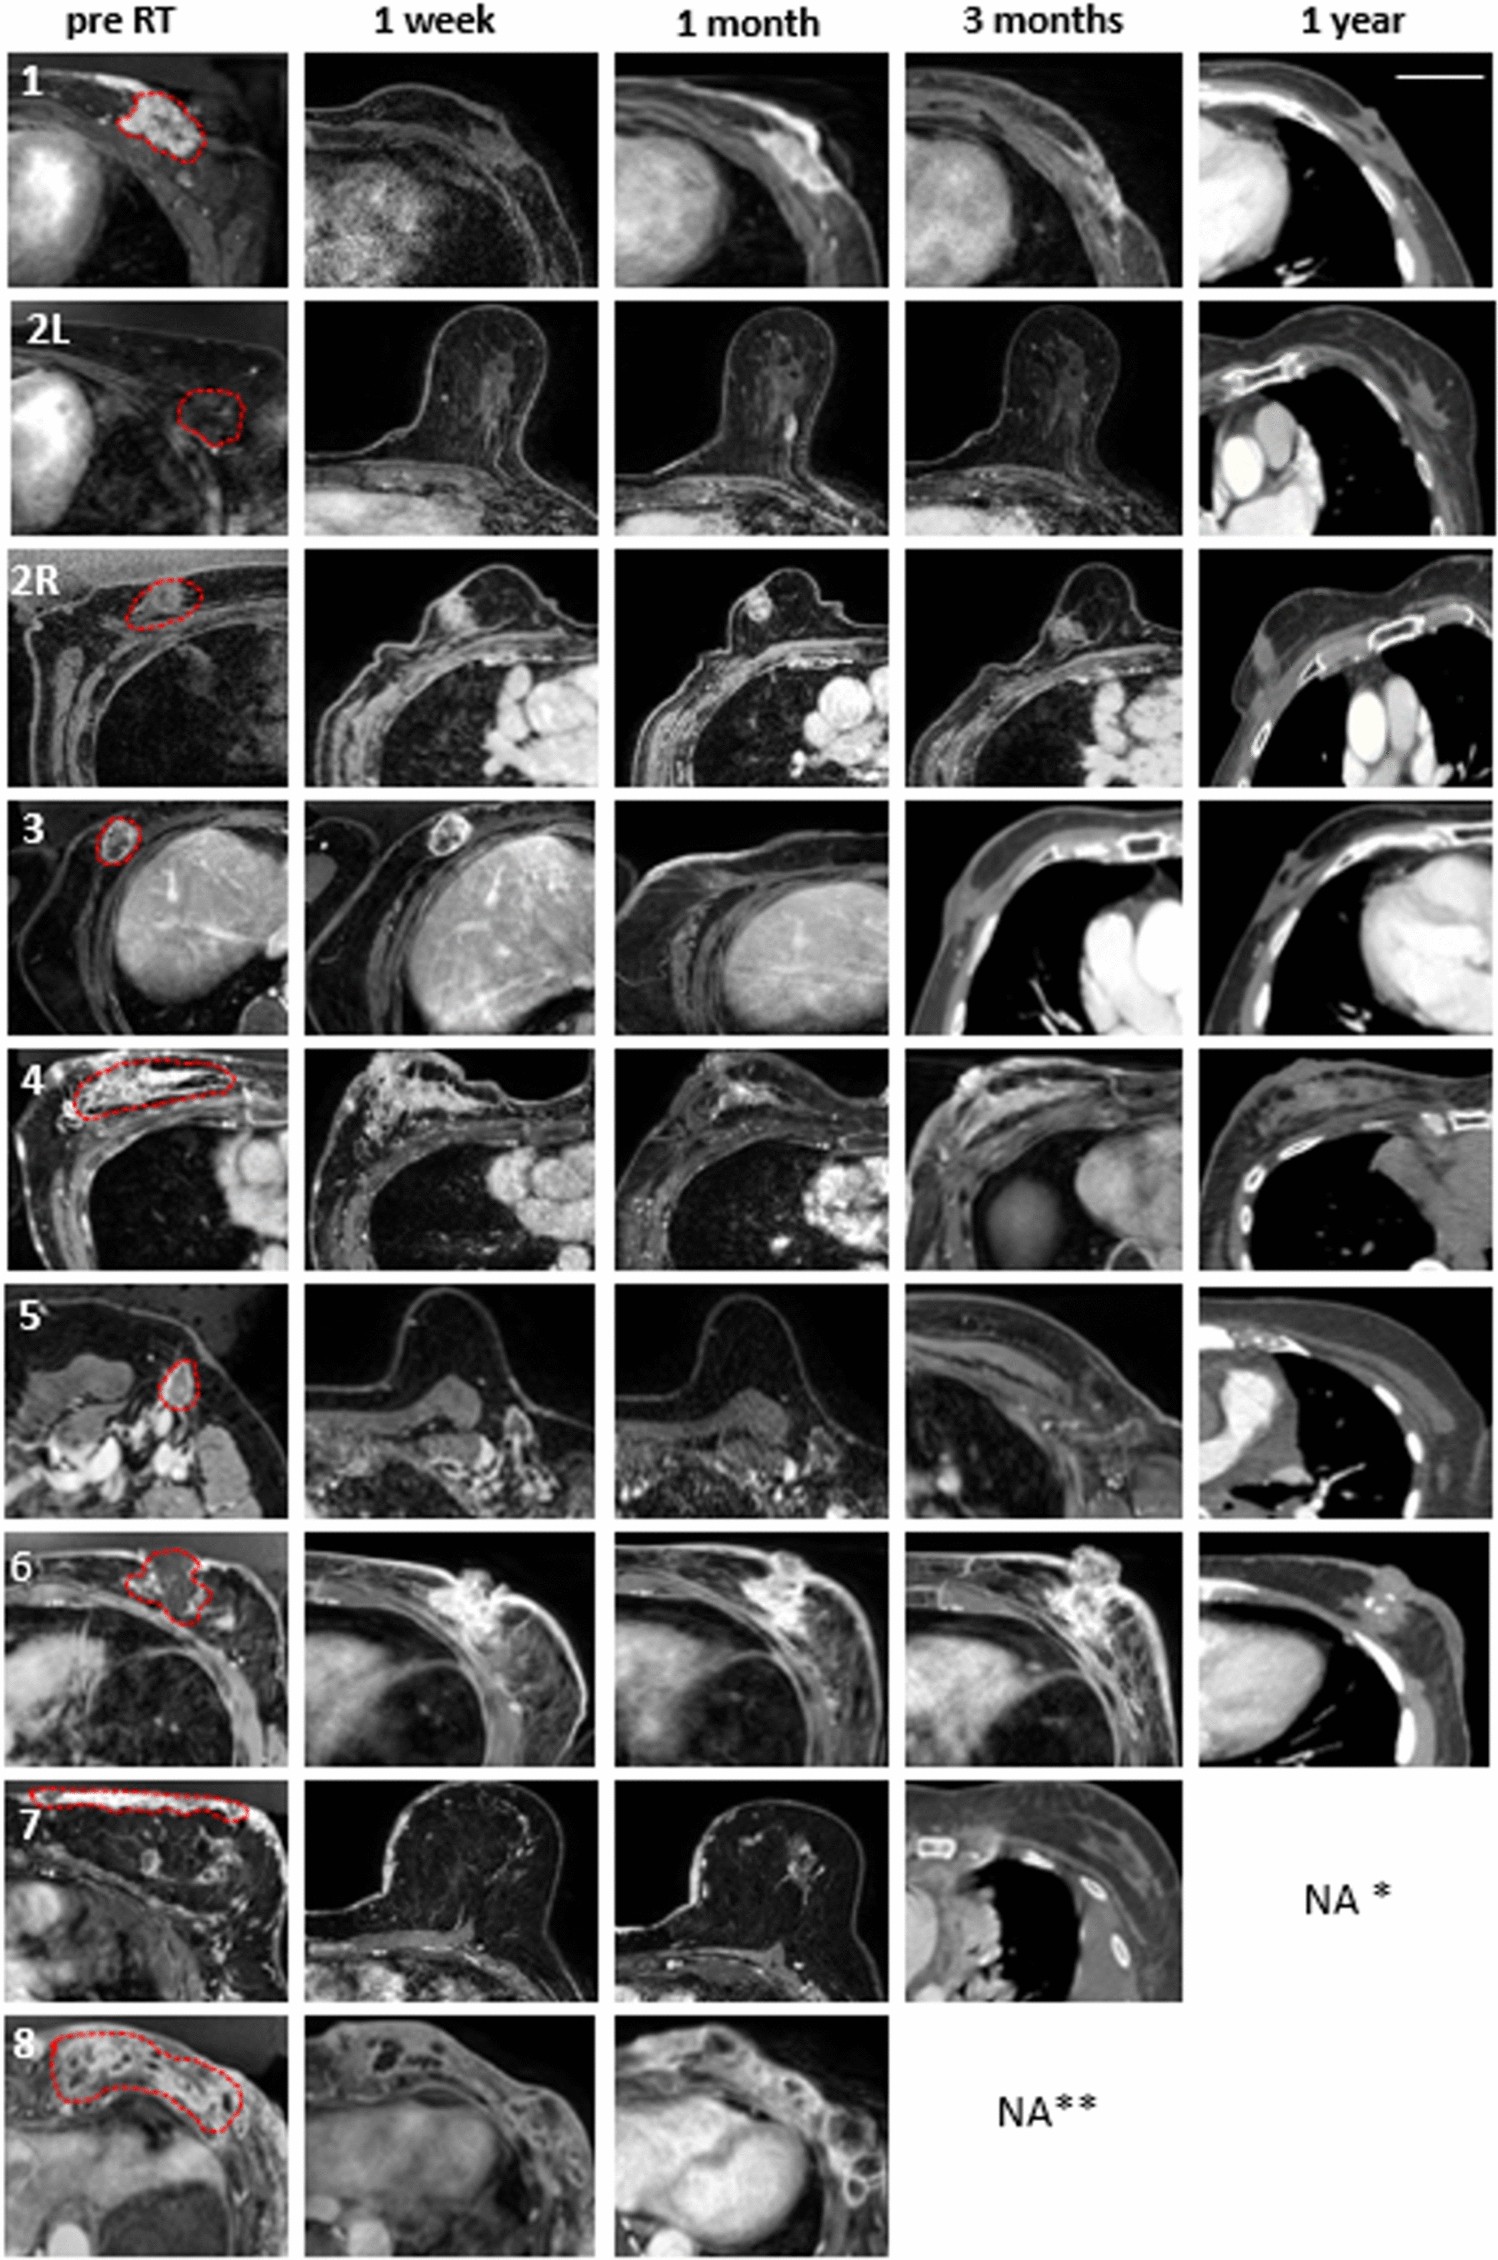

Figure 2

Individual tumour imaging before and after treatment The panel on the left represents pre-radiation target volume indicated, while the subsequent images show radiological outcomes with T1-weighted contrast-enhanced MRI at 1 week, 1 month, 3 months, and CT image at 1 year after treatment. *Patient 7 died of metastatic disease at 9 months (1-year follow-up not available), **Patent 8 died of metastatic disease at 3 months (3 months and 1-year follow-up not available). The scale on the top right figure represents an approximate size of 5 cm.